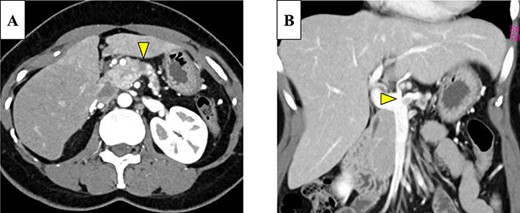

Abdominal-enhanced computed tomography (CT) revealed a low-density pancreatic body tumor of 25 mm in diameter, which was close to the gastroduodenal artery (GDA), and was accompanied by atrophy of the distal pancreatic parenchyma and dilation of the upstream MPD (Fig. 1A). Moreover, CT imaging of the portal phase revealed a filling defect within the splenic vein where it was in contact with the tumor (Fig. 1B). On magnetic resonance imaging, the tumor appeared as an area of signal hyperintensity on T2-weighted and diffusion-weighted images (Fig. 2A and B). On positron emission tomography-CT scan, the tumor exhibited greater uptake of 18F-fluorodeoxyglucose (Fig. 3). Although a definitive preoperative diagnosis could not be made, we suspected pancreatic ductal adenocarcinoma, and distal pancreatectomy with lymph node dissection was scheduled, without neoadjuvant chemotherapy, after obtaining consent from the patient. The pancreas was divided along the left edge of the GDA after mobilization of the artery; however, pathological examination of a frozen section of the pancreas stump was positive for PNET, and therefore a total pancreatectomy was performed (Fig. 4). The duration of surgery was 610 min, the intraoperative blood loss was 195 mL, and blood transfusion was not performed.

(A) Enhanced computed tomography (CT) showed a 25-mm nonhypervascular enhancing mass in the pancreatic body, which was accompanied by atrophy of the distal pancreatic parenchyma, and the upstream main pancreatic duct (MPD) was dilated to 11 mm in diameter (yellow arrow). (B) The mass also invaded the splenic vein (yellow arrow).